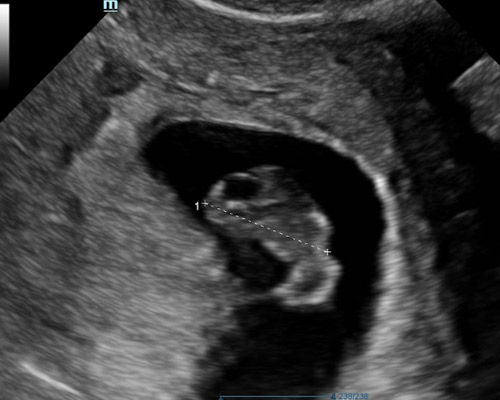

Typically carried out between 6 - 12 weeks, this scan uses ultrasound imaging to assess early development. It allows the sonographer to confirm that the pregnancy is located correctly, check for a heartbeat when visible, and measure the embryo to estimate how far along you are. It can also identify whether you are expecting more than one baby.

- A 2D ultrasound to confirm an intrauterine pregnancy

Sometimes it may be needed to perform a Transvaginal (Internal) scan for clear imaging in addition to abdominal scan, this involves inserting a thin probe into the vagina. It is safe and your consent will be obtained beforehand.